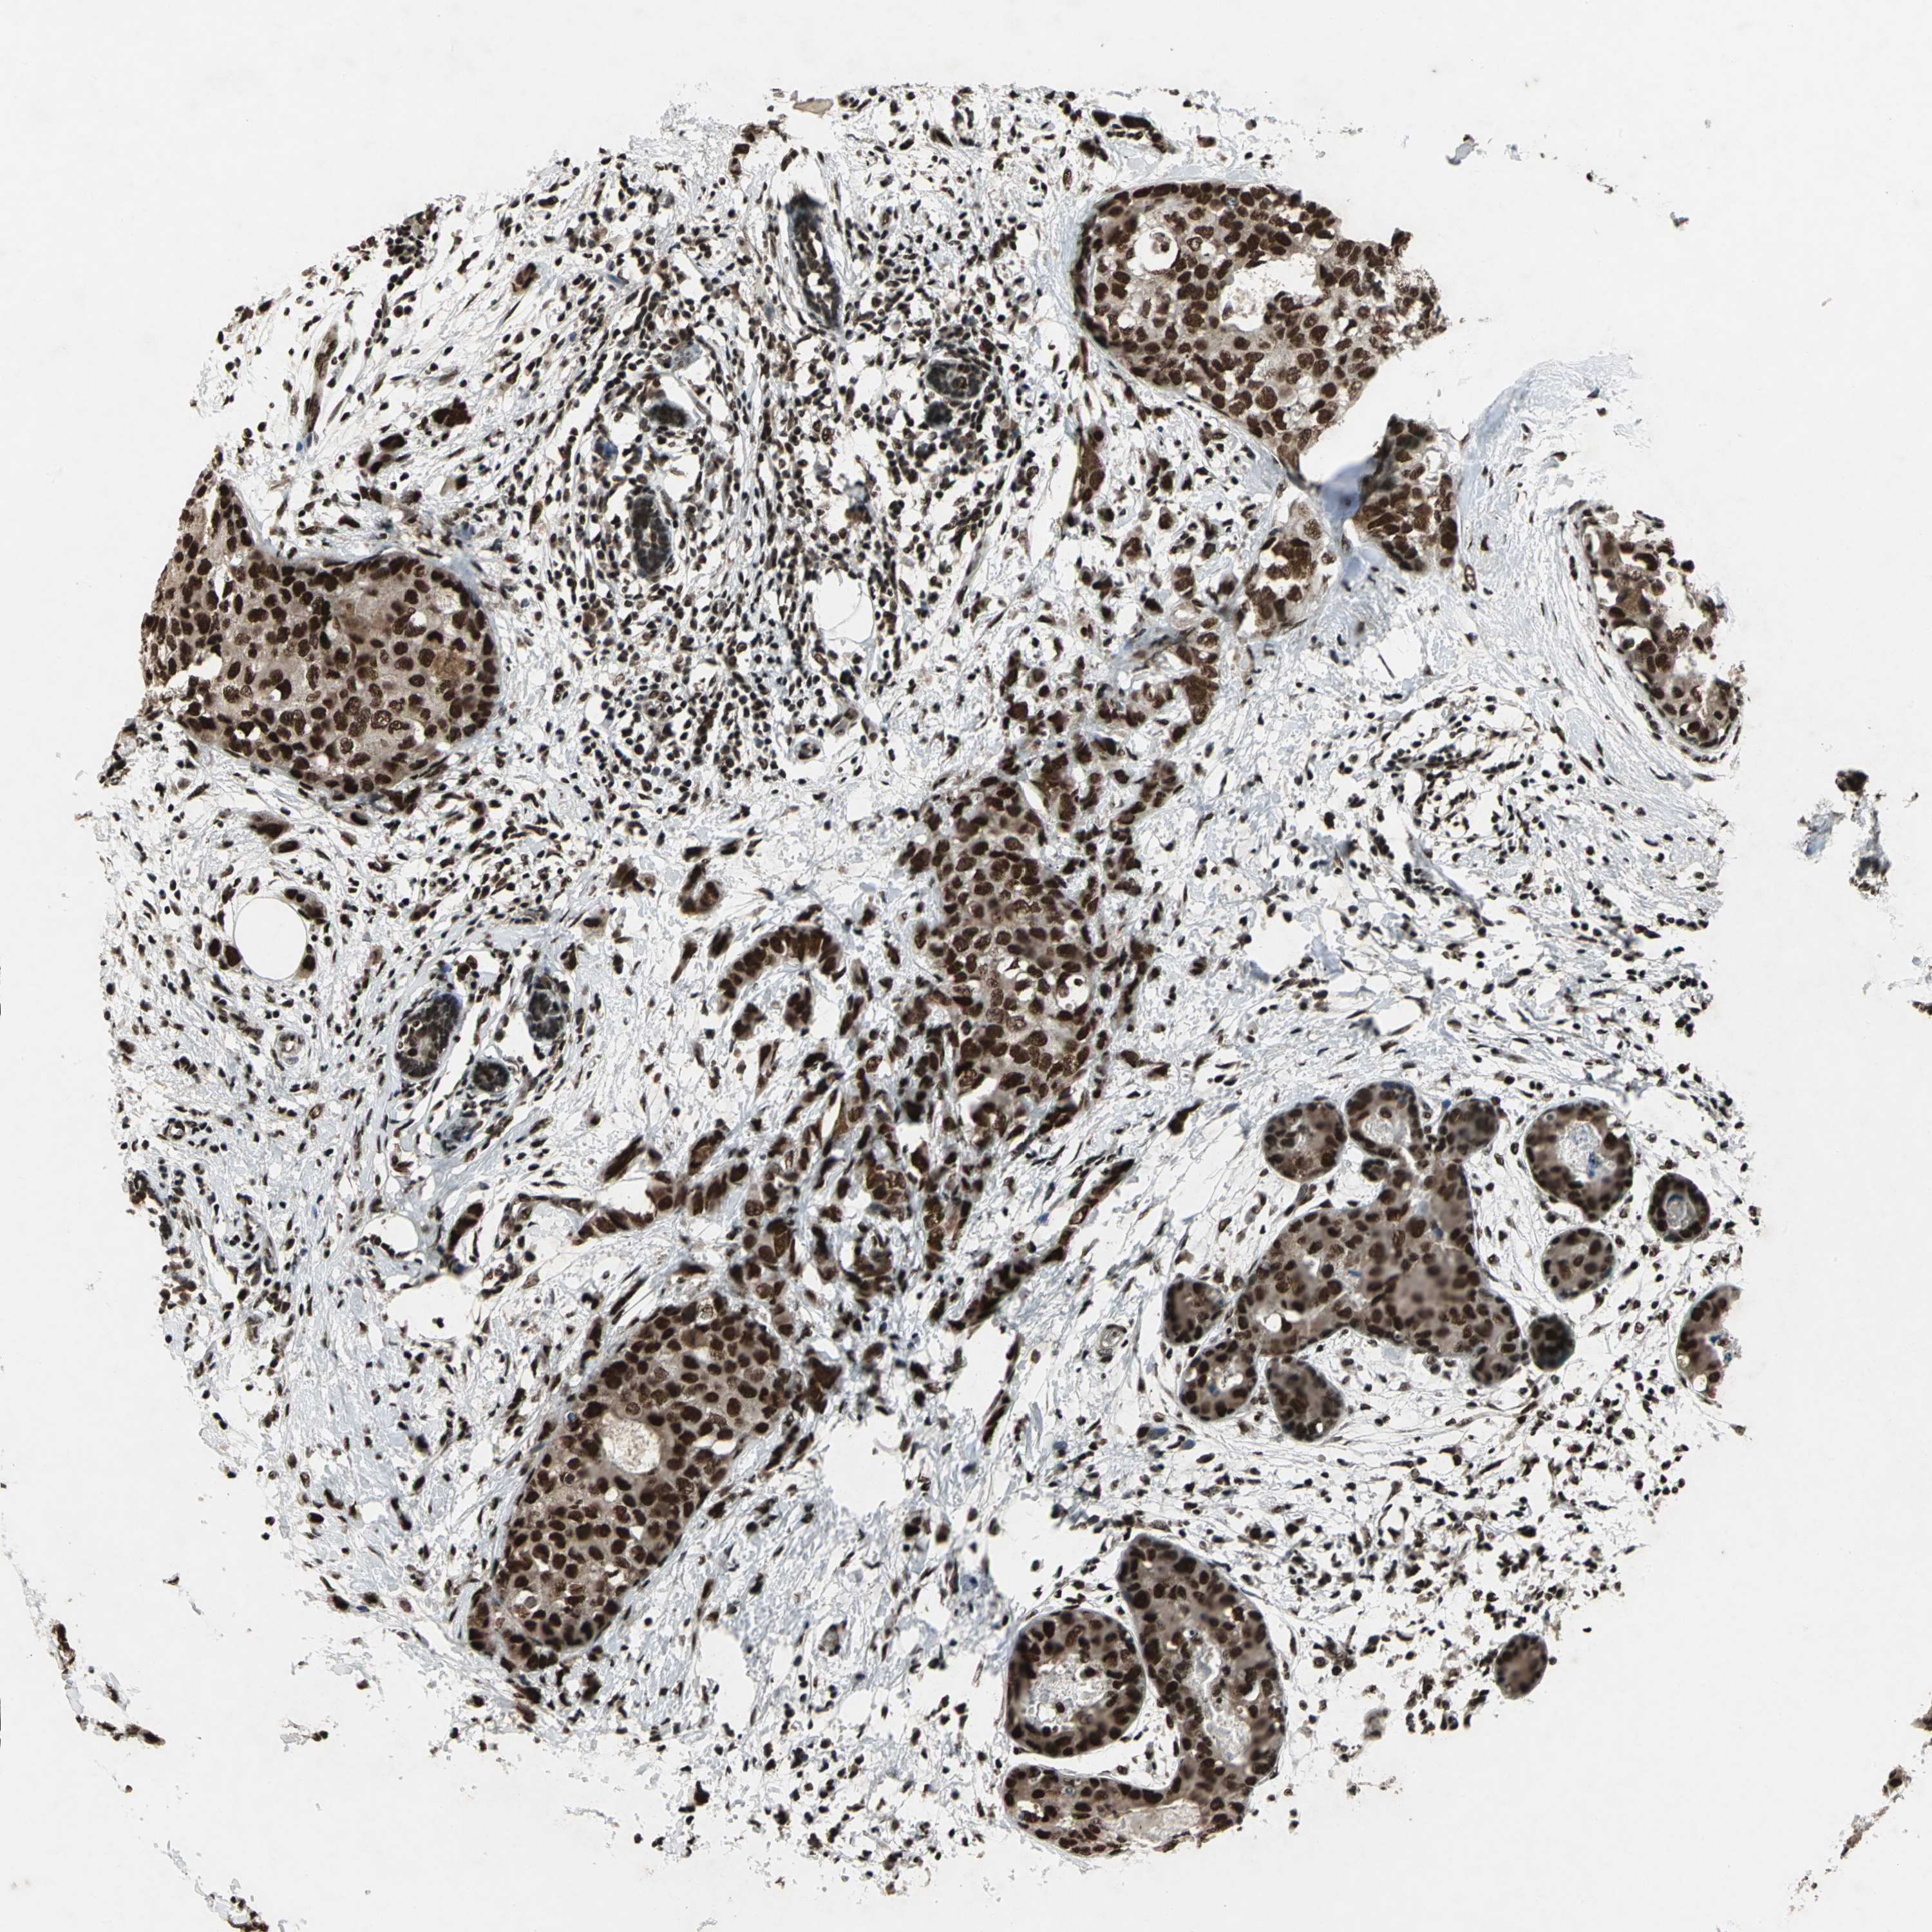

MTA2

CANCER BREAST CANCER Show tissue menu

BRCA TCGA BRCA VALIDATION PROTEIN EXPRESSION

Breast cancer

Human cancer